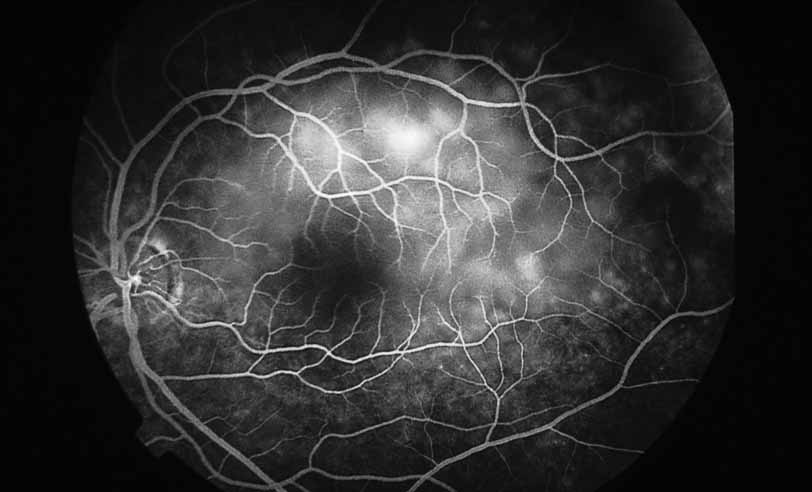

A third instance in which fluorescein angiography concentrating on the optic nerve may be helpful is in eyes with vascular engorgement of the optic nerve, especially with media opacities. Fluorescein angiography may help the clinician distinguish abnormally leaking capillaries from neovascularization. In acute multifocal hemorrhagic retinal vasculitis, optic nerve involvement is common in the early stages of the disease, 47 with optic nerve disc neovascularization seen later (see Figs. 10, 11, 12, and 13). Another fluorescein angiographic clue to the distinction between optic disc vessel engorgement and true neovascularization is the presence of associated large zones of retinal capillary nonperfusion such as those seen in sarcoidosis (see Figs. 14 and 15),34–40 acute multifocal hemorrhagic retinal vasculitis (see Figs. 10 and 11),47 or Eale disease (see Figs. 16 and 17).48–52

Fig. 14 Sarcoid retinal vasculitis. Color photograph demonstrates zones of periphlebitis along the course of retinal veins (Courtesy of Joseph Michaelson).

Fig. 15 Sarcoid retinal vasculitis. Fluorescein angiography demonstrates periphlebitis with staining along the course of retinal veins and capillary nonperfusion (Courtesy of Joseph Michaelson).